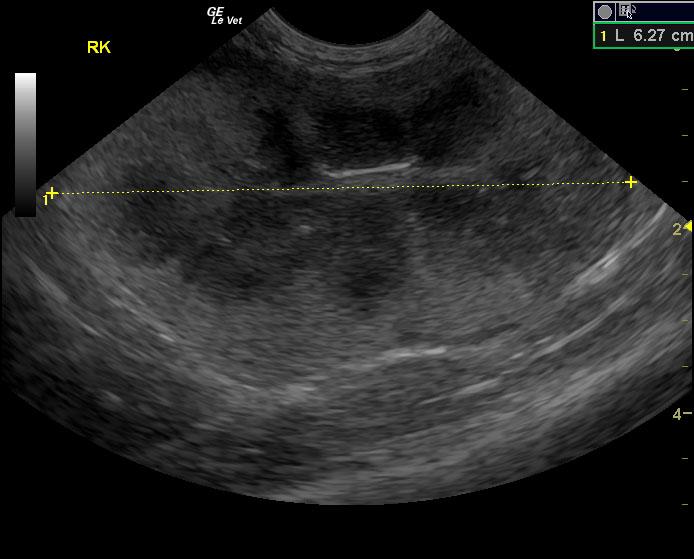

A seven-year-old MN DSH cat was presented with lethargy with the owner reporting that the cat’s behavior and temperament had changed. On urinalysis the urine was straw in color and clear; USPG was inappropriate (1.021), hematuria was present. The urine protein/creatinine ratio was 1.1. Abnormalities on CBC and serum chemistry were anemia, neutrophilia, lymphopenia, monocytosis, hypoproteinemia, and azotemia. Abdominal radiographs revealed an left nephromegaly and a mass effect in the gastrointestinal tract.